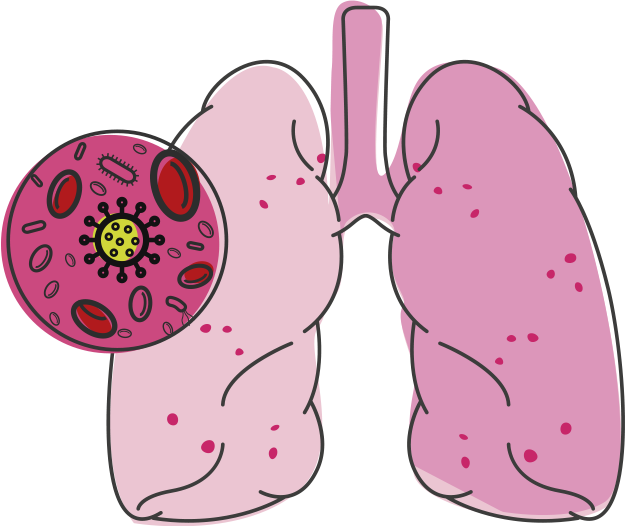

Sintomas mais característicos são tosse crônica, às vezes com raias de sangue, febre vespertina (no final do dia) e emagrecimento, que persistem por meses se não houver diagnóstico. Do pulmão a bactéria pode migrar, se não tratada, para outros locais do corpo causando outras lesões.

O tratamento é feito com antibióticos associados durante meses, dependendo das lesões e da condição física do paciente. O não tratamento, ou a interrupção do tratamento, pode levar a disseminação pelo organismo e a destruição dos pulmões acometidos.